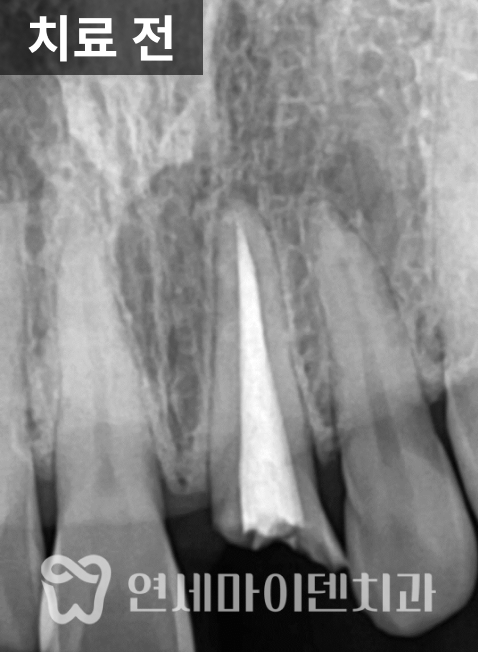

엑스레이를 확인해보니

일반적인 포스트가 아니라

캐스트 포스트가 깊게 삽입되어 있었고,

주변 신경치료 상태 역시

깔끔하게 마무리된 형태는 아니었습니다.

이러한 경우에는 단순 치근단 염증뿐 아니라

치근파절 가능성을 반드시 함께 고려해야 합니다.

잇몸에는 고름이 배출되는

소위 ‘잇몸 여드름’이 형성되어 있었는데,

그 위치가 치아의 상방 쪽에 자리하고 있었고

뿌리를 따라 세로 방향으로 뼈가 녹아 있는 양상이 관찰되었습니다.

이런 형태는 일반적인 염증보다

치근파절에서 자주 보이는 패턴으로,